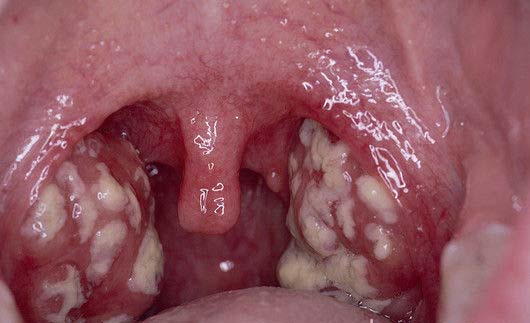

Фото - лакунарная ангина . Возможные осложнения при заболевании тонзиллитом . Острый тонзиллит не рекомендуется лечить антибиотиками, ведь они снижают местный иммунитет . А вот если форма заболевания более тяжелая, то больному необходим обязательный . . .

Острый тонзиллит

Острый тонзиллит у детей > Клинические рекомендации РФ . . .

Острый тонзиллит у детей, Союз педиатров России Кл . Категории МКБ: Острый тонзиллит неуточненный (J03 .9), Острый тонзиллит, вызванный другими уточненными возбудителями (J03 .8), Стрептококковый тонзиллит (J03 .0) .